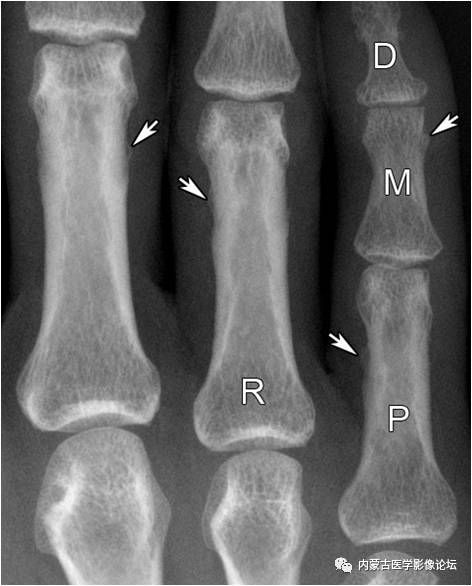

指骨正常骨突与骨嵴:白箭所示为肌腱附着的骨突与骨嵴,不应误为骨痂或骨膜增生。R:环指,P:近节指骨,M:中节指骨,D:远节指骨。